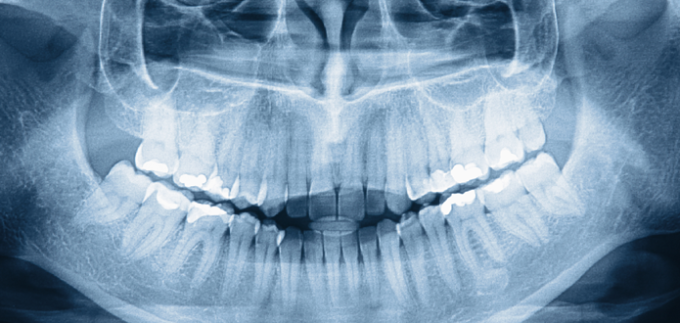

Odontologia general, ortodoncia, protesis fixa i remouble, implants dentals. Adults : Odontologia General i protesis. Nens Odontopedistria i Ondodoncia.